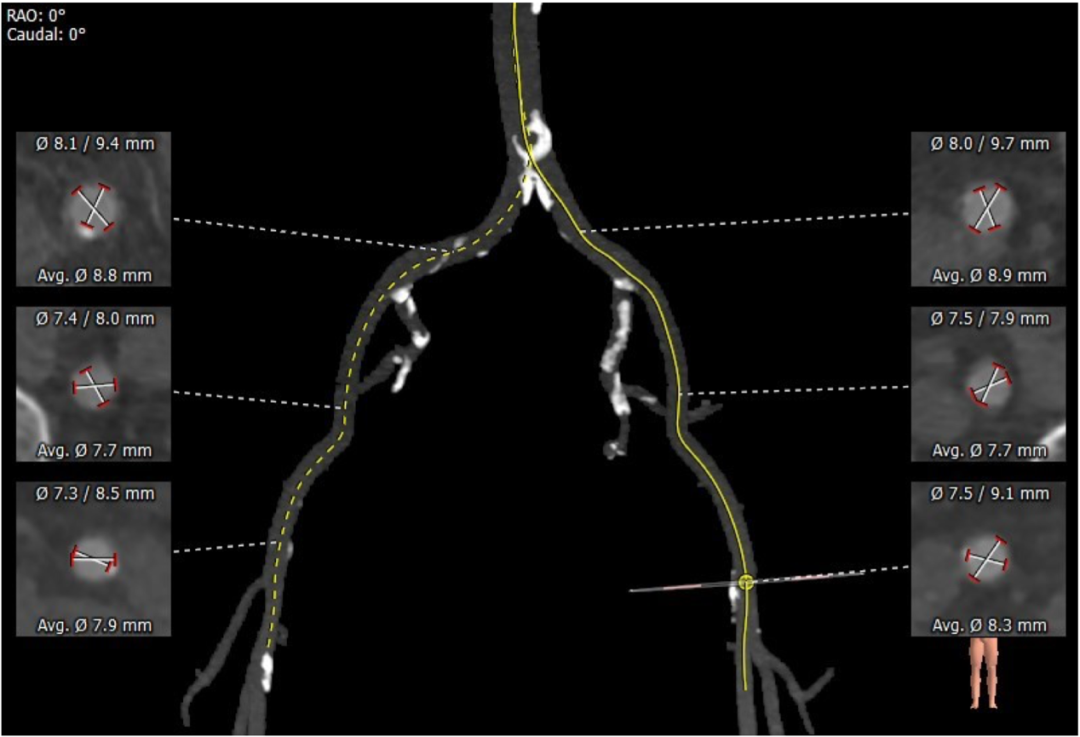

血管外周入路评估

入路血管少量钙化无其他病变,双侧血管内径良好,整体入路血管条件良好。